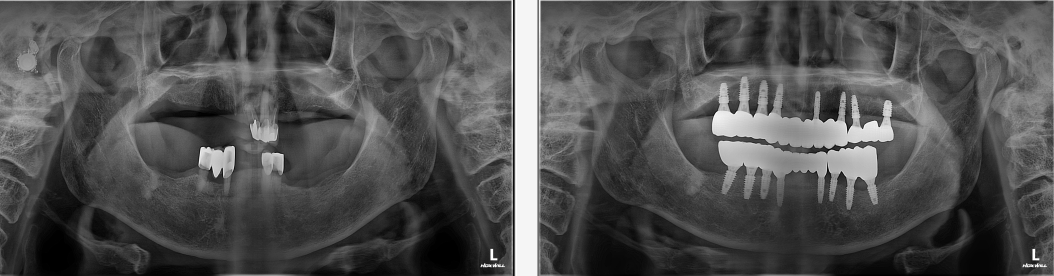

치료전후사진